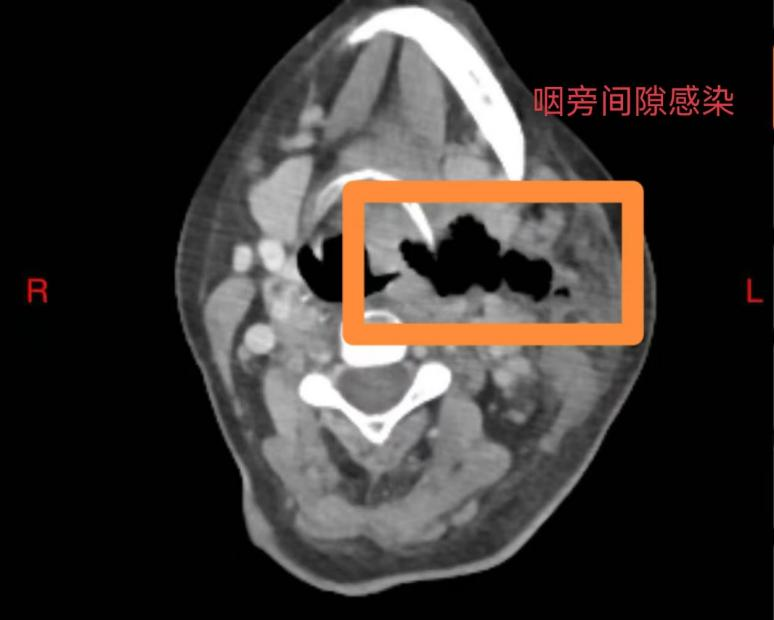

60岁的庄女士未曾想到,一场看似寻常的牙痛,竟会迅速发展为危及生命的重症。庄女士糖尿病多年未经规范治疗,口腔卫生欠佳,口内牙齿时不时疼痛、松动、脱落,患者总认为牙疼是小毛病,吃点甲硝唑就好了,从未重视。5 天前,左下后牙疼痛后患者依旧未经重视,很快就出现咽部、颈部疼痛伴吞咽困难,在当地医院接受抗感染治疗,病情却未见好转,还出现难以忍受的胸部疼痛,叠加吞咽、呼吸困难等症状,被救护车紧急送往西安市红会医院耳鼻咽喉头颈整形修复科。经诊断,庄女士为 “颞下、咽旁、翼下颌、颌下间隙感染,颈部坏死性筋膜炎、下行性坏死性纵膈炎”,病情及其危重,需要头颈外科、胸外科、内分泌科等多学科联合救治,此类疾病非常凶险,死亡率较高,为患者办理住院后转入急诊重症监护室(EICU),一场与死神的赛跑就此拉开序幕。

咽旁间隙感染

耳鼻咽喉头颈整形修复科龚龙岗主任、马戈副主任团队第一时间全面评估病情,发现庄女士不仅存在口腔颌面多间隙感染,还并发左侧颈部坏死性筋膜炎、下行性坏死性纵膈炎、右侧包裹性脓胸,叠加2型糖尿病(血糖控制不佳)、高血压病1级(极高危)、电解质紊乱等基础疾病与并发症,病情复杂凶险。面对这一局面,科室迅速启动多学科联合救治机制,一场跨科室的协同作战即刻展开 —— 胸部外科、EICU、内分泌代谢科、神经内科、营养膳食科等科室专家迅速集结,从各自专业维度切入,共同为庄女士制定个性化救治方案。